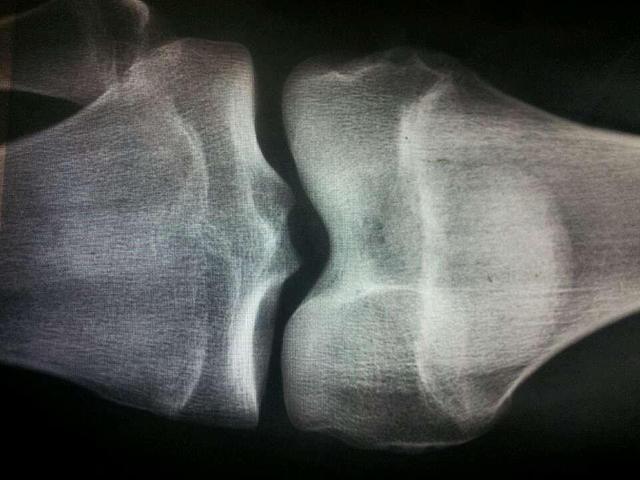

如何避免骨骼线过早愈合?

如果想要长高一些,就要从以下两方面入手,避免骨骼线过早的愈合。

1、补钙要适量,特别是避免过量,因为过量的钙质会促进骨骼线骨化闭合,身高停止生长;

2、避免吃激素含量高的营养品,因为大量的激素会使人出现早熟、骨骼线提前闭合的情况,所以平时要少吃动物内脏、炸鸡等食物。